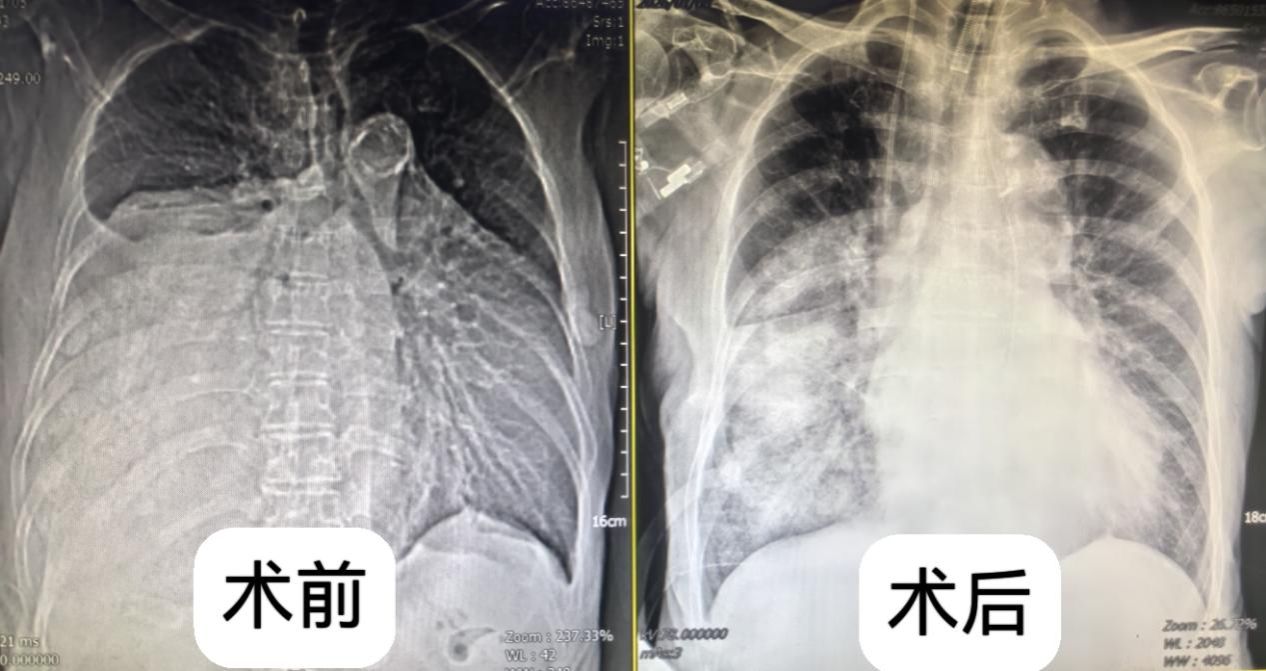

一年前,叶奶奶在体检中偶然发现纵隔占位性病变,当时肿瘤直径约 4 厘米,因无明显不适症状,且考虑到年龄较大,家属选择了保守观察。然而近半年来,患者逐渐出现活动后气喘、心慌等症状,近期更是发展到体力无法支撑正常行走,体重也随之下降。复查胸部 CT 显示,肿瘤已增至超过15厘米,占据右侧胸腔超过2/3空间,严重压迫心脏、大血管及食管,且与周围组织粘连致密,若不及时干预,随时可能因呼吸循环衰竭危及生命。

术中精细操作 + 术后科学康复 多学科全程护航

术后,患者被立即转入急诊 ICU 进行严密监护。ICU 团队针对高龄患者术后恢复特点,实施了 “个体化呼吸支持 + 早期活动” 方案:术后 6 小时便协助患者翻身拍背,12 小时开始床上肢体活动,24 小时成功拔除气管插管,逐步过渡到自主呼吸。术后第3天患者便能下床活动,咳嗽、气喘等症状完全缓解,顺利转回普通病房;术后12天,各项指标均恢复正常,达到出院标准。